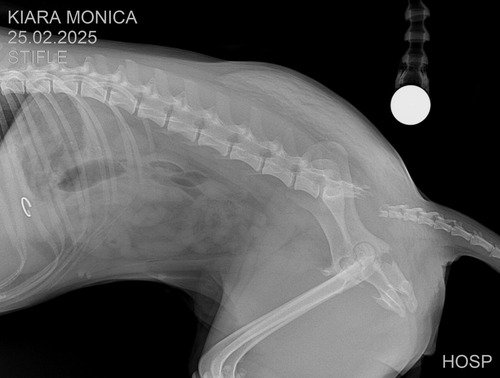

Kiara fez diversos exames e foram constado 3 fraturas, sendo necessário amputação da calda e cirurgia bilateral do quadril